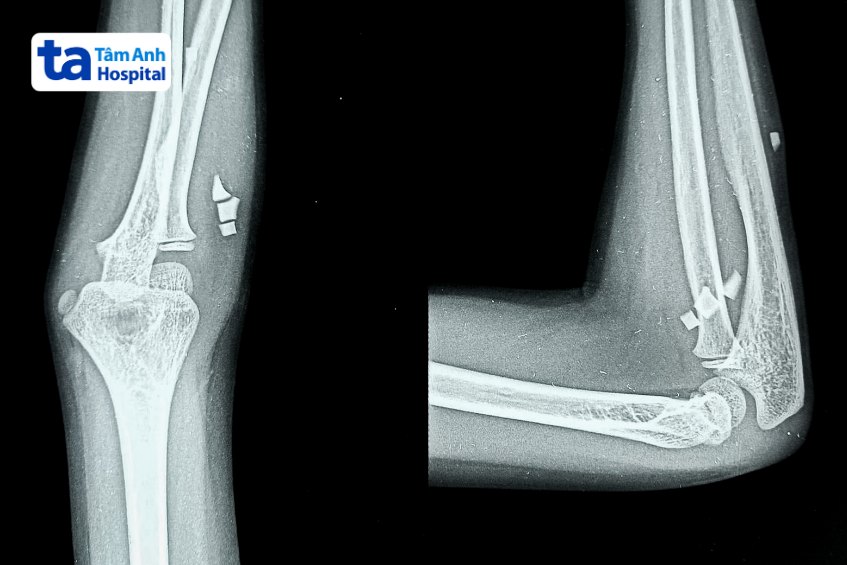

Chụp X quang khuỷu tay là kỹ thuật chẩn đoán hình ảnh sử dụng tia bức xạ X để tạo ra hình ảnh cấu trúc bên trong của khuỷu tay. Hình chụp X quang thể hiện khớp khuỷu tay có màu trắng, do canxi trong xương hấp thụ nhiều tia bức xạ hơn so với mô mềm xung quanh. Thông qua hình chụp X quang khuỷu tay, bác sĩ có thể phát hiện và chẩn đoán nguyên nhân gây tổn thương khuỷu tay.

Kết quả từ phim chụp X quang giúp bác sĩ quan sát cấu trúc ở khuỷu tay. Thông qua đó, bác sĩ có thể phát hiện và chẩn đoán tình trạng nứt xương, gãy xương, lệch khớp, u khớp hay các vấn đề khác…

X quang khuỷu tay cũng là cách để phát hiện sớm bệnh lý liên quan đến khớp khuỷu như thoái hóa khớp, viêm khớp dạng thấp, bệnh gút, viêm khớp vảy nến, viêm bao hoạt dịch… Từ đó, bác sĩ có thể đề xuất phương pháp can thiệp kịp thời, giúp người bệnh ngăn ngừa biến chứng nguy hiểm về sau.